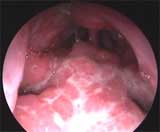

Вид аденоидных вегетаций III степени при осмотре задних отделов полости носа эндоскопом 0° (осмотр через левую половину носа).

Аденоидные вегетации III степени, блок задних отделов полости носа (риноскопия — эндоскоп 0°).